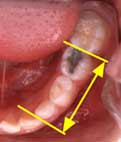

乳歯の虫歯で6歳臼歯が前に寄ってきた場合

虫歯も不正咬合の大きな原因の一つです。おとなの歯は、前の歯によりかかりながら生える性質を持っています。ですから、むし歯などで乳歯の前後が、かけてしまうと、6歳臼歯は生えるときに、前に寄ってきてしまいます。 6歳臼歯が前に寄ってきてしまうと、6歳臼歯の前の乳歯が抜けてから生えかわる大人の歯が、生える場所が足りなくなって、でこぼこになることがあります。 |